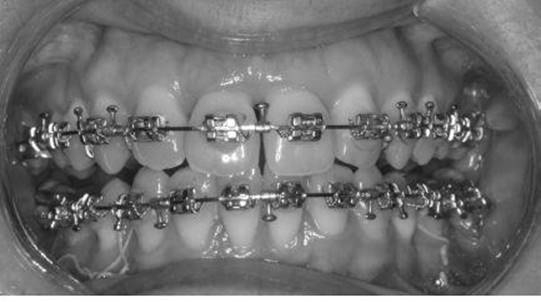

Towards the end of the presurgical phase, upper and lower rectangular archwires should be in position and surgical hooks or soldered brass wires are added in the midline and throughout the buccal segments (Figure 4.15). These provide a means of attaching temporary intermaxillary fixation during surgery. They can also be used to attach seating elastics or intermaxillary elastics during the immediate postoperative period.

Figure 4.15 Rectangular archwires with surgical hooks. Note the archwires are engaged in the brackets using stainless steel ligatures.